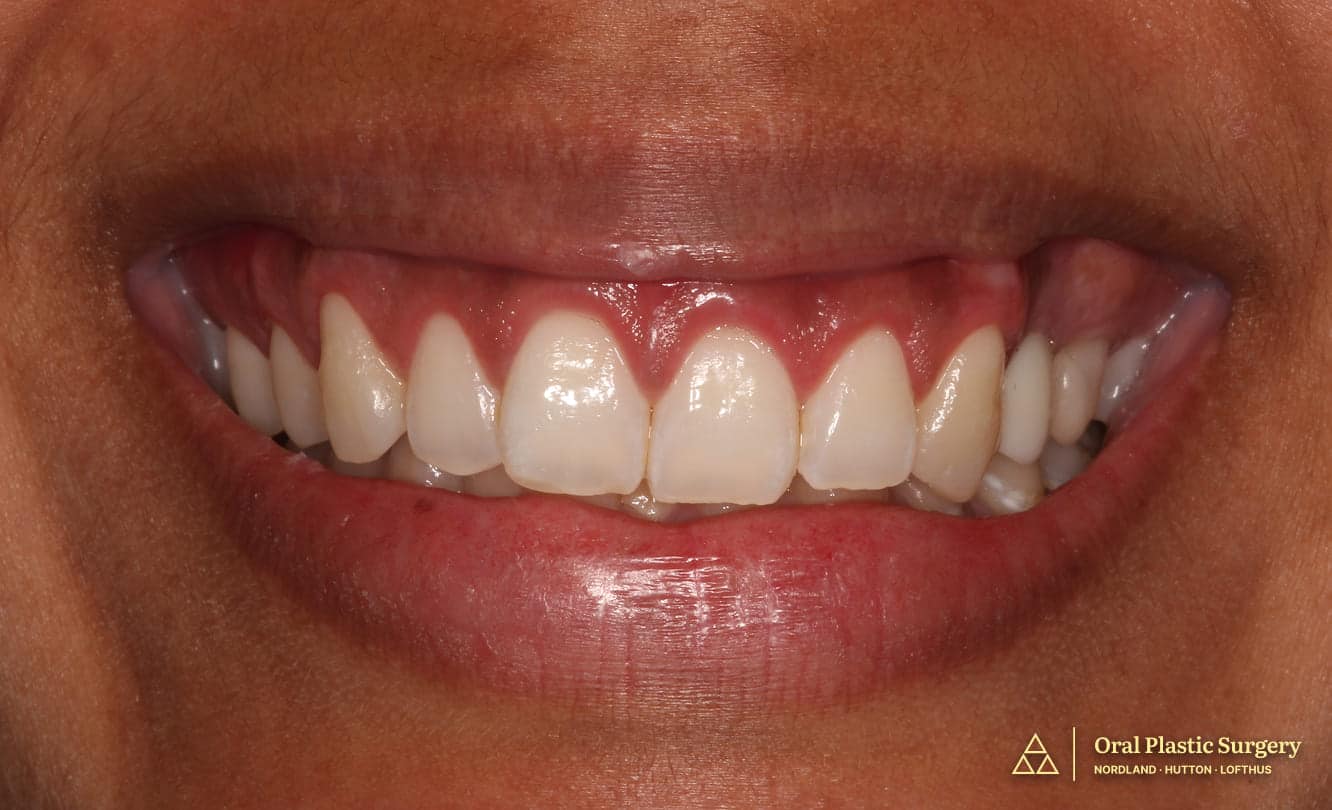

Outcome

Jennifer healed beautifully at every stage. The ridge augmentation created the bone volume needed for implant placement, and the implant integrated predictably. There were no complications, and the final result was stable and healthy.

The final implant crown blended naturally with her neighboring teeth. The tooth looked proportionate, symmetrical, and realistic in the smile, with an emergence profile that appeared natural rather than artificial.

Most importantly, the final result did not look like “an implant.” It looked like her own tooth had always been there.

For Jennifer, the biggest win was freedom.

After living with a removable flipper for a decade, she finally had a tooth that felt secure, permanent, and effortless. She could smile, talk, and laugh without thinking about whether her temporary tooth was shifting, coming loose, or drawing attention.

The result restored not only her smile, but also her confidence.

Final implant restoration demonstrating natural emergence profile, ideal tissue architecture, and symmetric integration with adjacent dentition. The result is indistinguishable from a natural tooth.